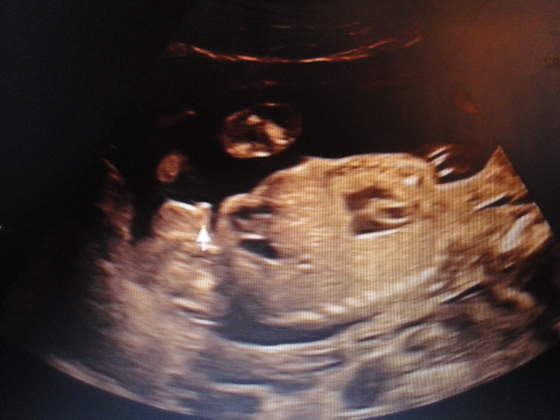

1400 mego Szczęścia

Zobacz załącznik 610714Zobacz załącznik 610715Zobacz załącznik 610716